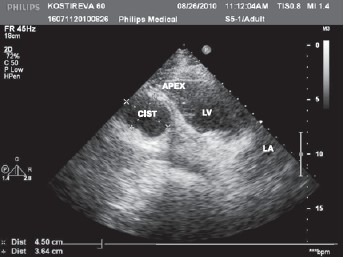

Приобретенная кистаперикарда в нашей практике обнаружена у пациента Б., 55 лет, перенесшего операцию двойного аортокоронарного шунтирования передней межжелудочковой и правой коронарных артерий. Спустя 10 лет пациент поступил в наш центр с явлениями рецидива стенокардии. При рентгеноскопии органов грудной клетки обнаружена округлая интенсивная тень размерами 8х12х9 см с четкими контурами, тесно прилегающая к заднебоковой стенке ЛЖ. Предложено дифференцировать диагноз между кистой, истинной и ложной аневризмой ЛЖ. Трансторакальная ЭхоКГ позволила выявить зоны гипокинезии миокарда задней и латеральной стенок ЛЖ на среднем и апикальном уровнях, снижение фракции выброса до 36%. Вдоль заднебоковой стенки сердца отмечено неоднородное по плотности, с фестончатым наружным краем образование размерами 6,8х3,0х2,6 см (рис. 5). Такое изображение без четко очерченной капсулы резко отличалось от всех описанных ранее, имело разнородное по эхогенности содержимое, что соответствовало понятию «рамолиционной» кисты (киста «от размягчения» послеоперационной гематомы в этой области).

Рисунок 5. Двухмерная ЭхоКг пациента Б., 55 лет.

Диагноз: состояние после 2 операций АКШ в 1987 г., приобретенная киста перикарда (указана стрелками). АКШ аортокоронарное шунтирование; А — аорта.

Такого рода киста является еще и травматической по своей сути, так как развилась после операционной травмы. Рамолиционные кисты образуются в компактной ткани при очаговом омертвении ее (при кровоизлиянии, воспалении, некрозе, инфаркте) и последующем размягчении, разжижении и резорбции нежизнеспособного субстрата. Стенка такой кисты образована тканью органа, в котором она локализуется. В дальнейшем киста может замениться соединительной тканью. При чреспищеводной ЭхоКГ это образование находилось вне оптимального поля обзора.

Больному выполнена операция повторного АКШ (переднемежжелудочковой артерии и задней межже- лудочковой ветви) и удаления приобретенной кисты. В ходе операции выявлено, что по всей заднебоковой поверхности ЛЖ находится спаянное со стенкой плотное образование. Стенка кисты представлена плотной фиброзно-мышечной тканью, просвет содержит старые тромботические массы, фибрин и гемолизированную кровь. Площадь кисты составляла 9х11 см, после удаления ее стенка ЛЖ оставалась неровной и бугристой.